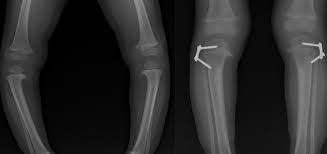

تقوص الركب يمنع هاجر من العودة للمدرسة

الام ايمان تروي دامعة العين على طفلتها هاجر التي تعاني من تقوص في الركب نتيجة لنقص الكالسيوم جراء سوء التغذية كان الوضع المعيشي للاسرةسببا من الاسباب التي تلاحقها

البوم هاجر تتوق شوقا لعودتها للمدرسة مندفعه من جديد للحياة